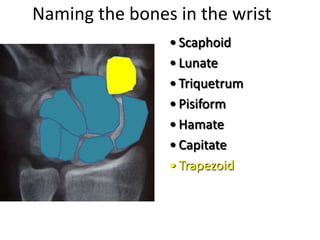

- Naming the bones, joints, tendons, nerves and skin landmarks of the hand and wrist.